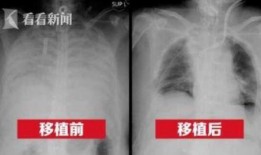

港媒最新爆料新冠肺病人,新冠肺病患者真实生活与康复历程”

最近港媒可是爆出了一个大新闻,让人不禁瞪大了眼睛!说的是新冠肺病人的一些最新情况,听起来是不是有点刺激?那就跟着我一起,来揭开这...